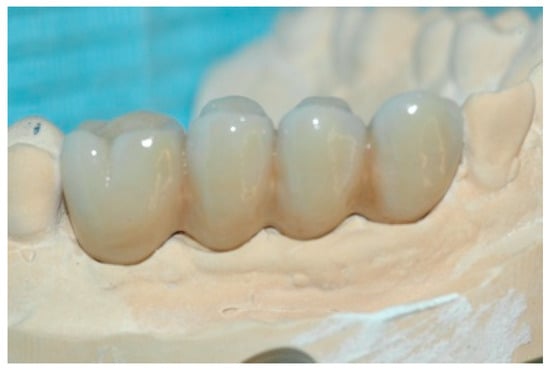

On the basis of the impression taken, the model was developed and a wax structure was created according to the prosthetic planning and the position of the implants on a model developed with removable soft gingiva (Figure 7).

Figure 7. Impression and structure made.

Prosthesis 02 00023 g007